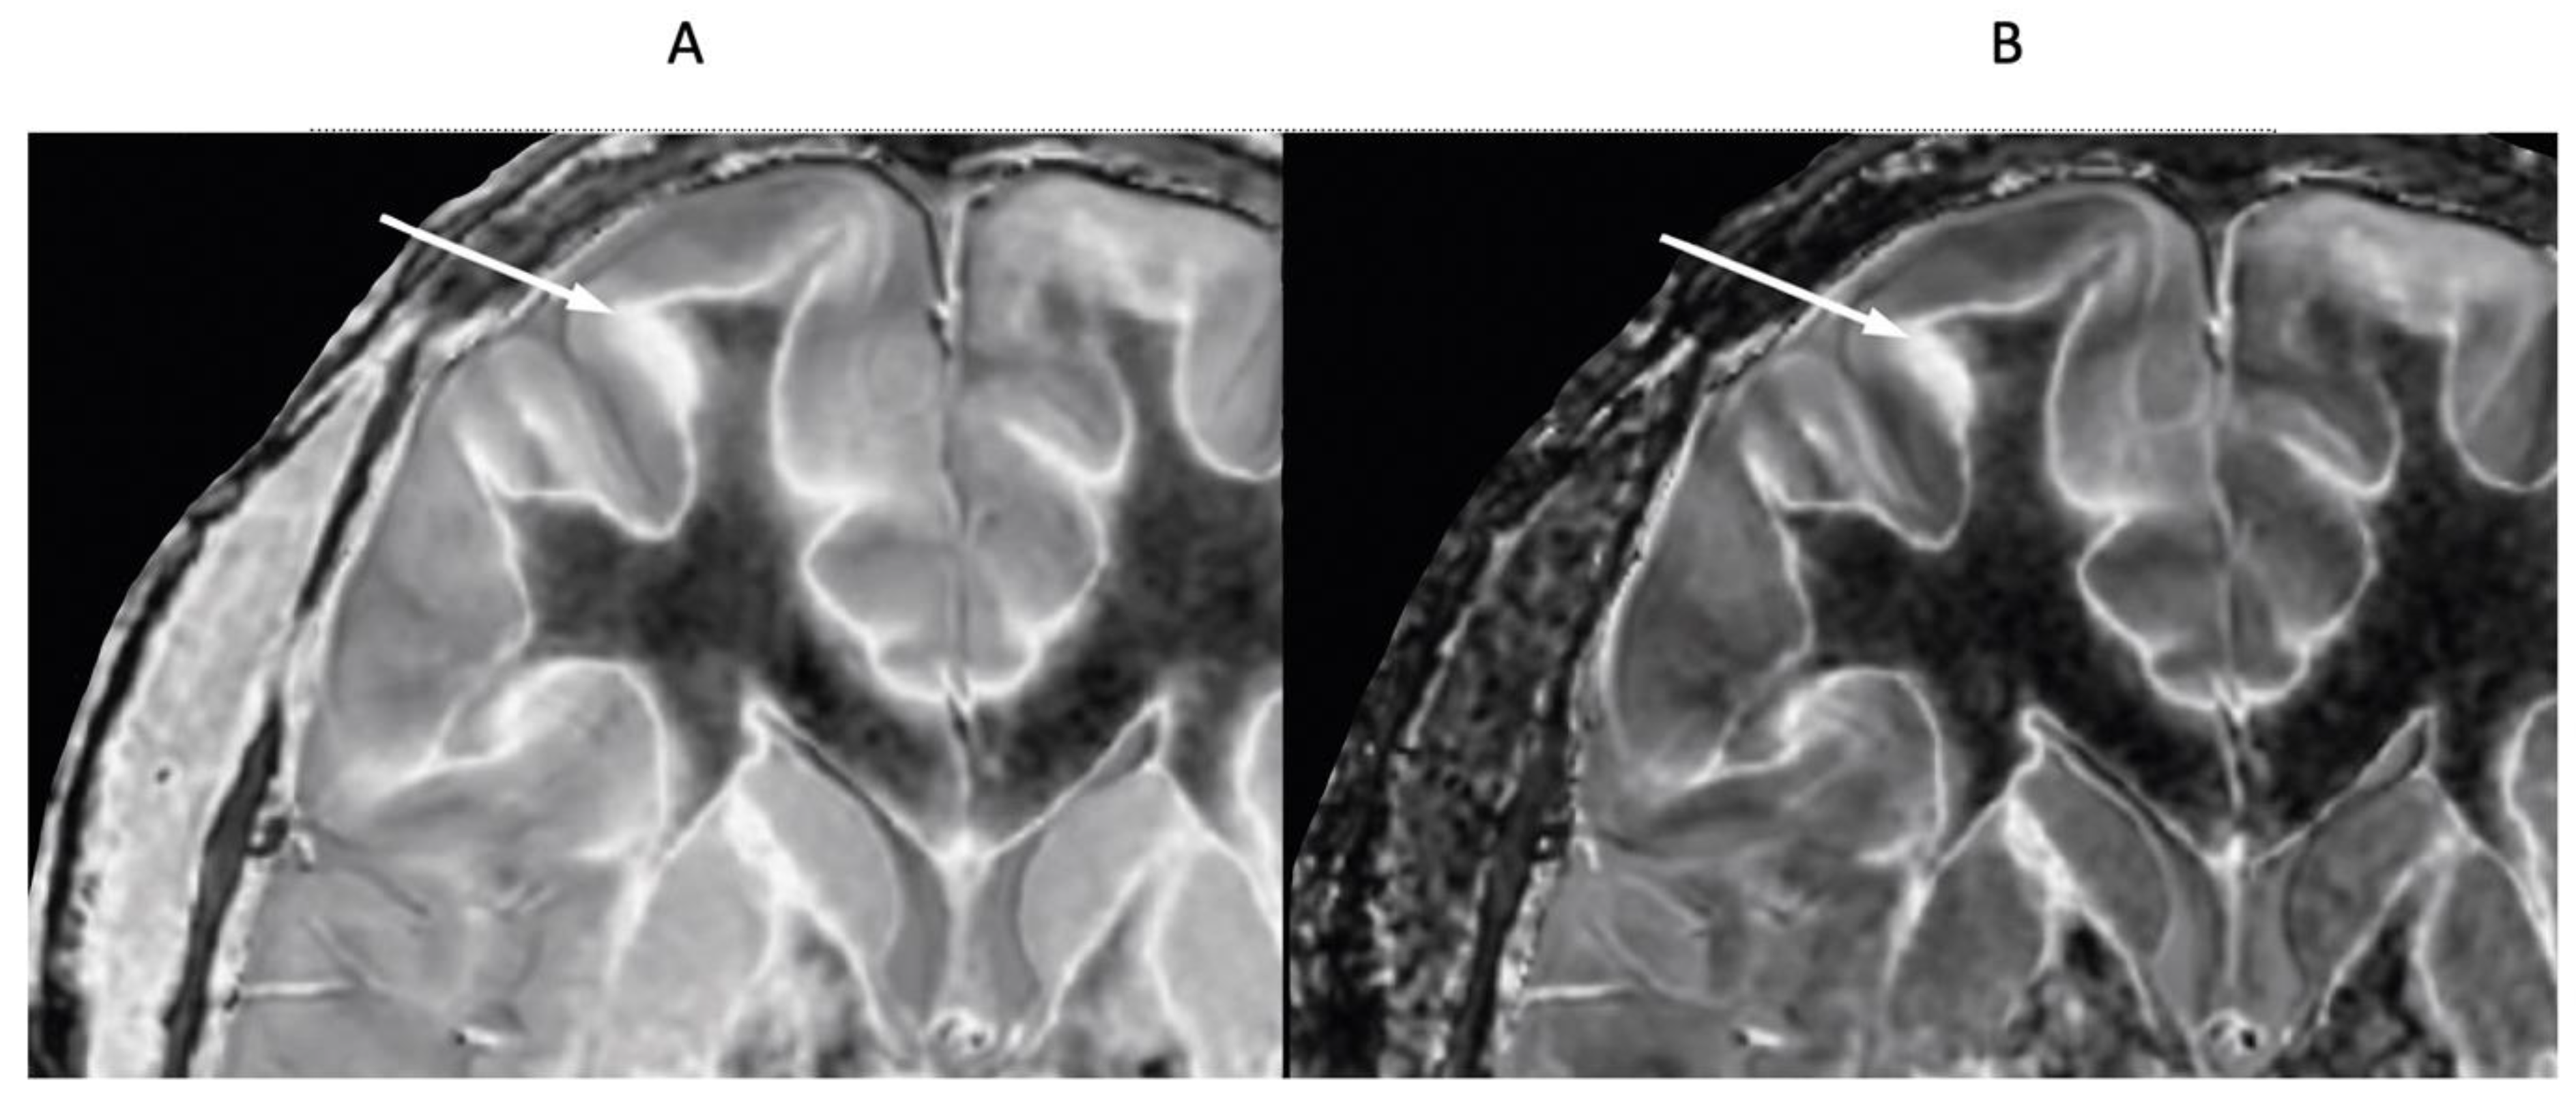

Figure 23.

41-year-old female patient with MS. A leukocortical lesion in the right medial frontal region is shown on the narrow mD dSIR (T1-BLAIR) image (A) and a matching lSIR image (B) (arrows). There are also left to right profiles with signal plotted against position (in mm) for the dSIR (blue) and lSIR (orange) images (C) at the level of the horizontal arrows shown in (A) and (B). No boundary between white matter and gray matter is seen within the lesion in (A). A disrupted high signal boundary between white matter and gray matter is seen in the lesion in (B). The lSIR profile (orange) has higher signal and steeper slopes than the dSIR profile (blue) in (C). The difference in signal (or contrast) achieved for the same change in position is generally greater with the lSIR filter i.e., the contrast shown on the lSIR image generally has a higher spatial resolution.